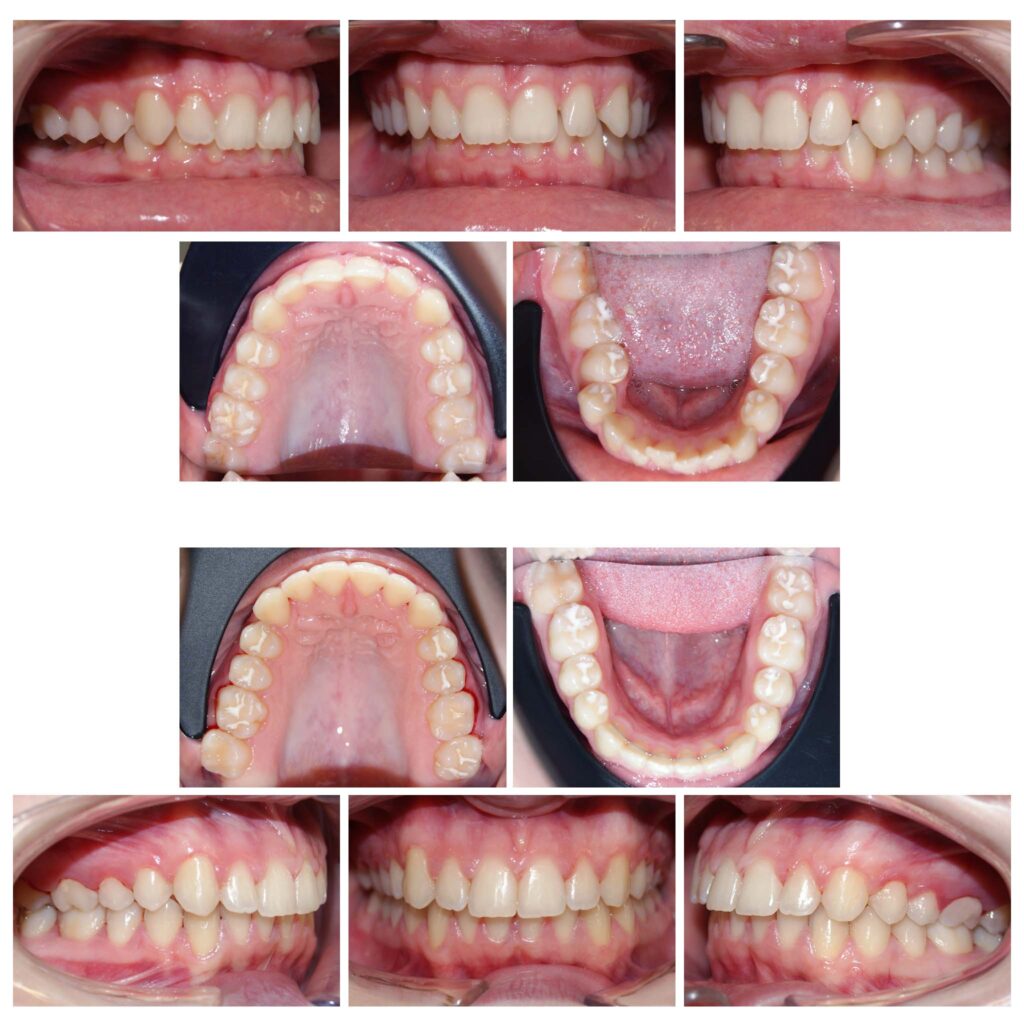

Ocluzie încrucișată | Ancoraj pe mini implante | Brackets | Simetrizarea conturului zâmbetului